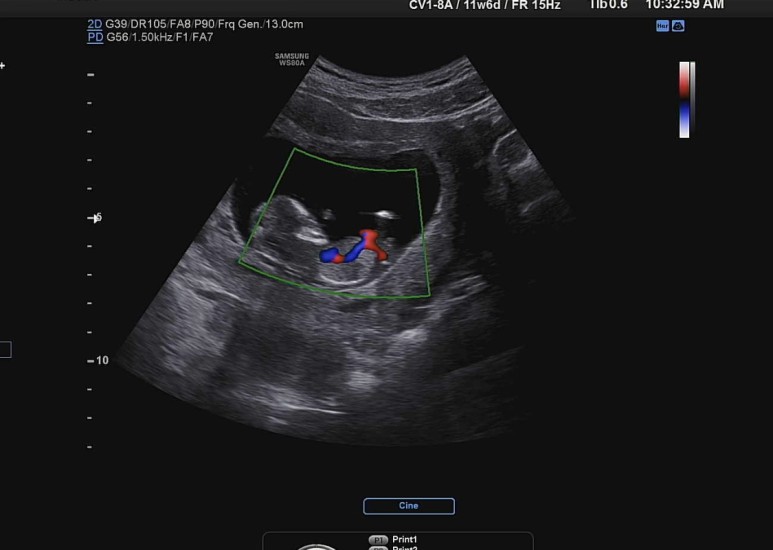

기본적으로 심장이 잘 뛰고 있는지도 보고ㅡ,

꿀잠이 오늘의 바이탈은 141bpm !

(태아 12주 평균 심장 박동수는 120~180bpm, 으로 평균 150bpm 이라고 한다)

심장으로 혈액이 잘 흘러 들어가고 있는지 색깔을 통해 확인.